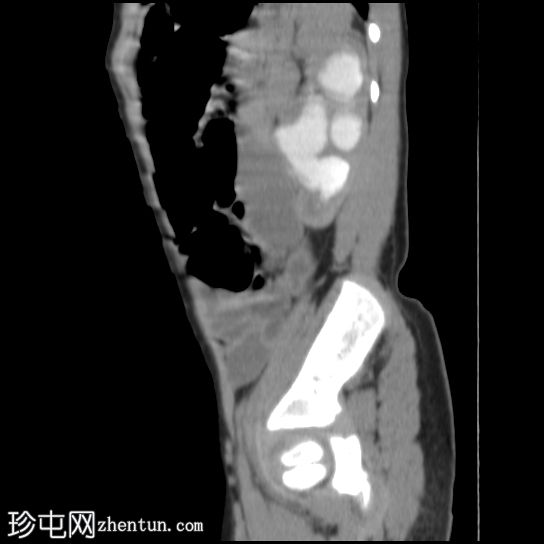

肾矢状位

排泄期

左侧肾盂肾盏系统中度扩张;但未见明确的放射性结石。

右肾未见异常。

影像

学表现最可能为左侧肾盂输尿管连接部梗阻。